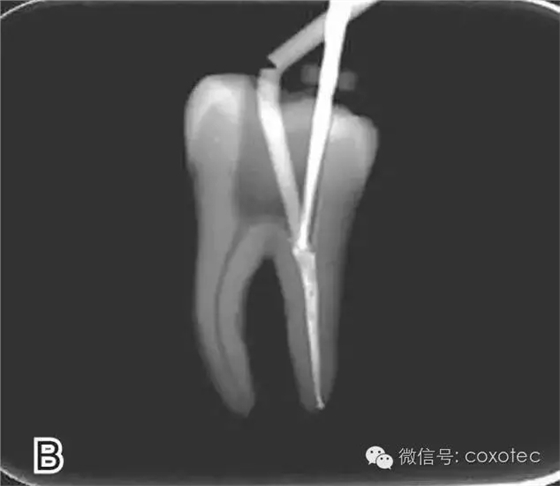

以下本文摘自網(wǎng)絡,對連續(xù)波熱牙膠充填技術的操作通俗易懂,以供臨床醫(yī)生學習和參考。感謝原作者辛苦制作和分享。 前言:連續(xù)波熱牙膠充填技術是目前臨床上應用最廣泛的一種熱牙膠充填技術,其將熱牙膠垂直加壓充填技術的多步加熱和加壓改良為加熱加壓同時完成,簡化了充填步驟,提高了充填效率。本文將介紹其具體操作步驟。 操作步驟 根據(jù)預備后根管的粗細選擇相應型號的攜熱器工作尖。 要求工作尖能自由到達距根尖4~5 mm(有學者提出3~4 mm)的位置并能輕微接觸根管壁,用橡皮片做好標記(圖1) 圖1 選擇攜熱器工作尖,A.試攜熱器尖 B.工作尖在根內的位置